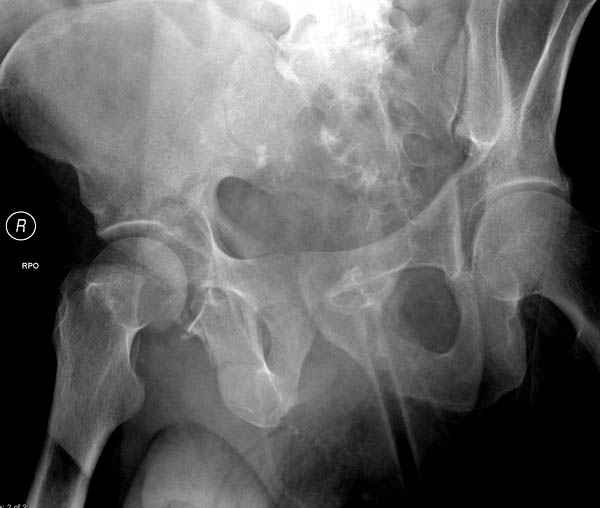

Дополнительно имеется перелом ацетабулума: задняя

колонна с полупоперечным переломом, и переломы костей лица.

На седьмой день зафиксирован перелом ацетабулума через задний доступ. Перед операцией для профилактики DVT, IVC фильтер, также получает Lovenox.

По снимку создается впечатление о высоком поперечном переломе, задней колонны, стенки; почему не пользовались *magic screw*?